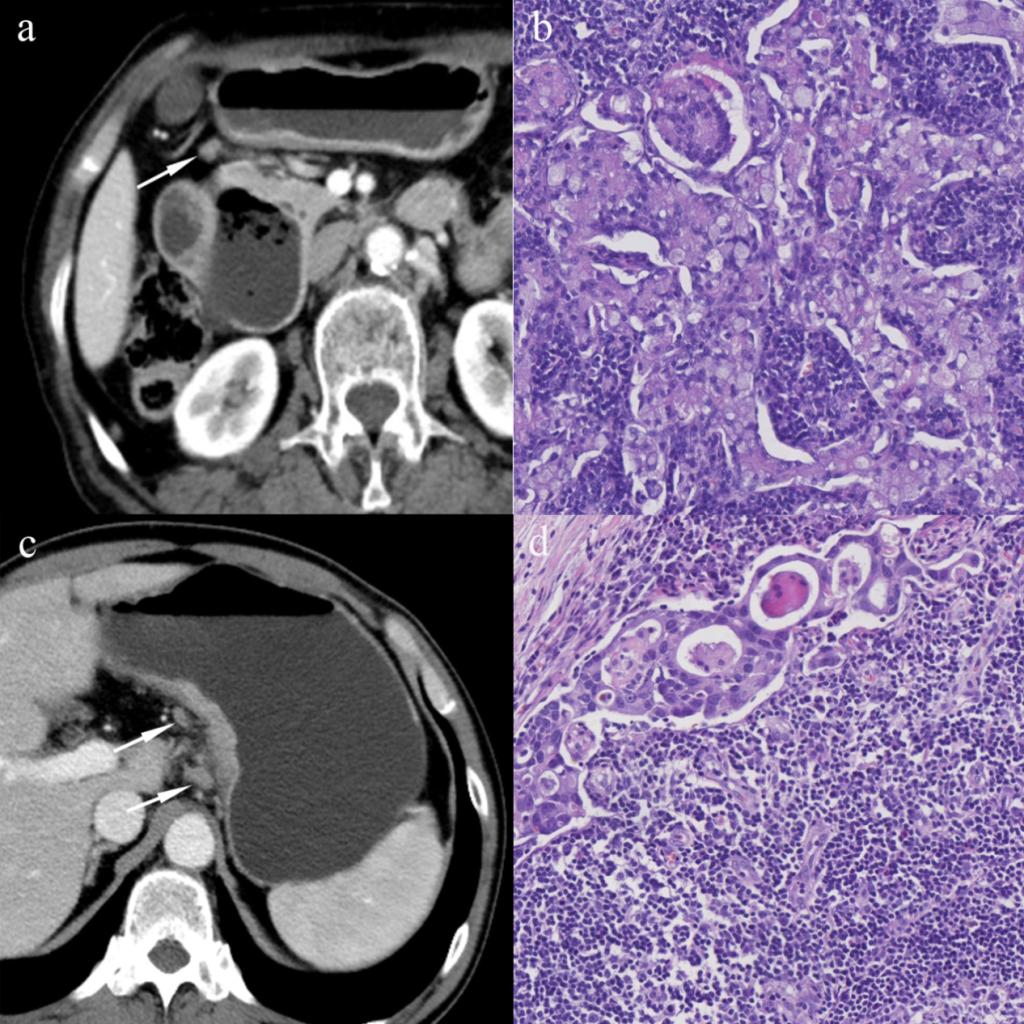

圖1 區(qū)域淋巴結(jié)的CT及病理影像